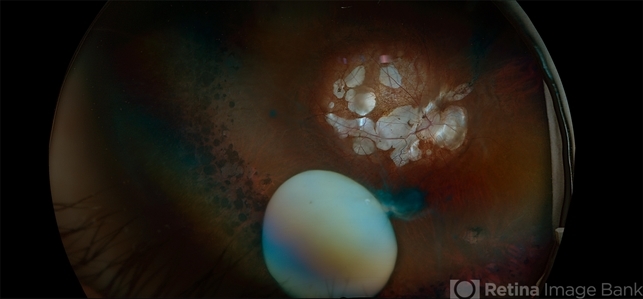

- Subluxation of the Lens, myopic degeneration, lattice degeneration, posterior staphyloma, peripapillary atrophy

- Ultra-wide field fundus photos of an 53-year-old man with a Subluxation of the Lens in the posterior vitreous cavity of the right eye after a trauma that happened many years ago. Patient remains stable with no adverse reaction to the lens at this time. No surgical intervention is recommended at this time. Patient also has myopic degeneration and lattice degeneration that will require patient to have follow up care.